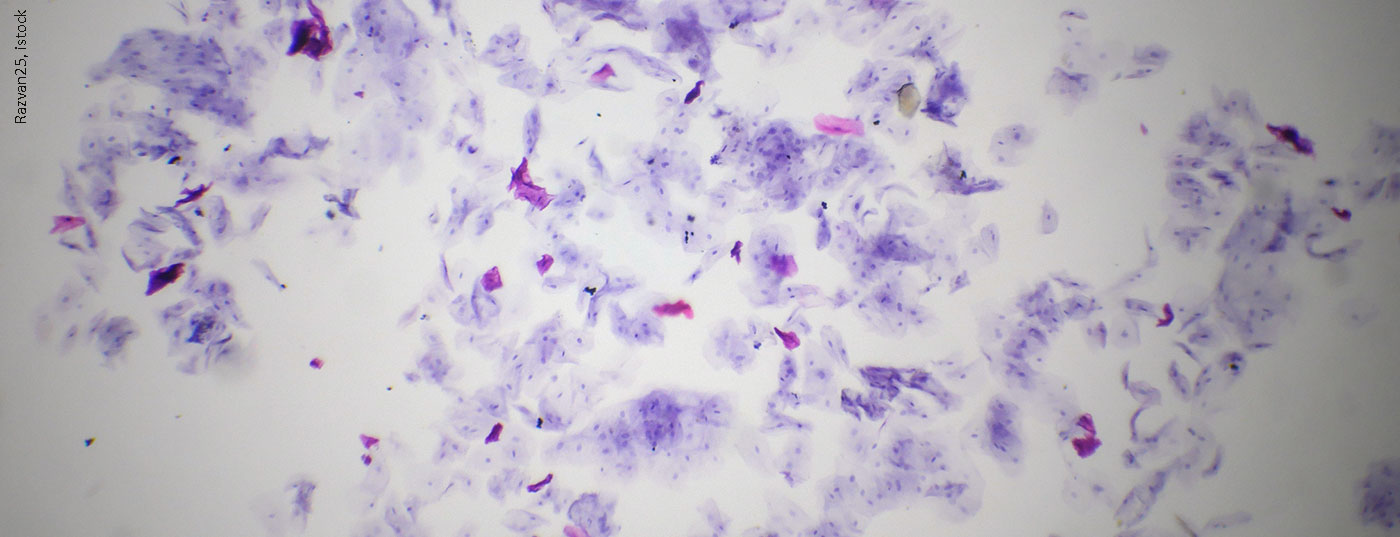

Läsionen der Mukosa können lokal begrenzte Ursachen haben, aber auch Symptome von systemischen Erkrankungen sein. So sind Veränderungen der Mundschleimhaut unter anderem auch Merkmale vieler Hauterkrankungen und infektiöser Dermatosen.

Läsionen der Mukosa können lokal begrenzte Ursachen haben, aber auch Symptome von systemischen Erkrankungen sein. So sind Veränderungen der Mundschleimhaut unter anderem auch Merkmale vieler Hauterkrankungen und infektiöser Dermatosen.